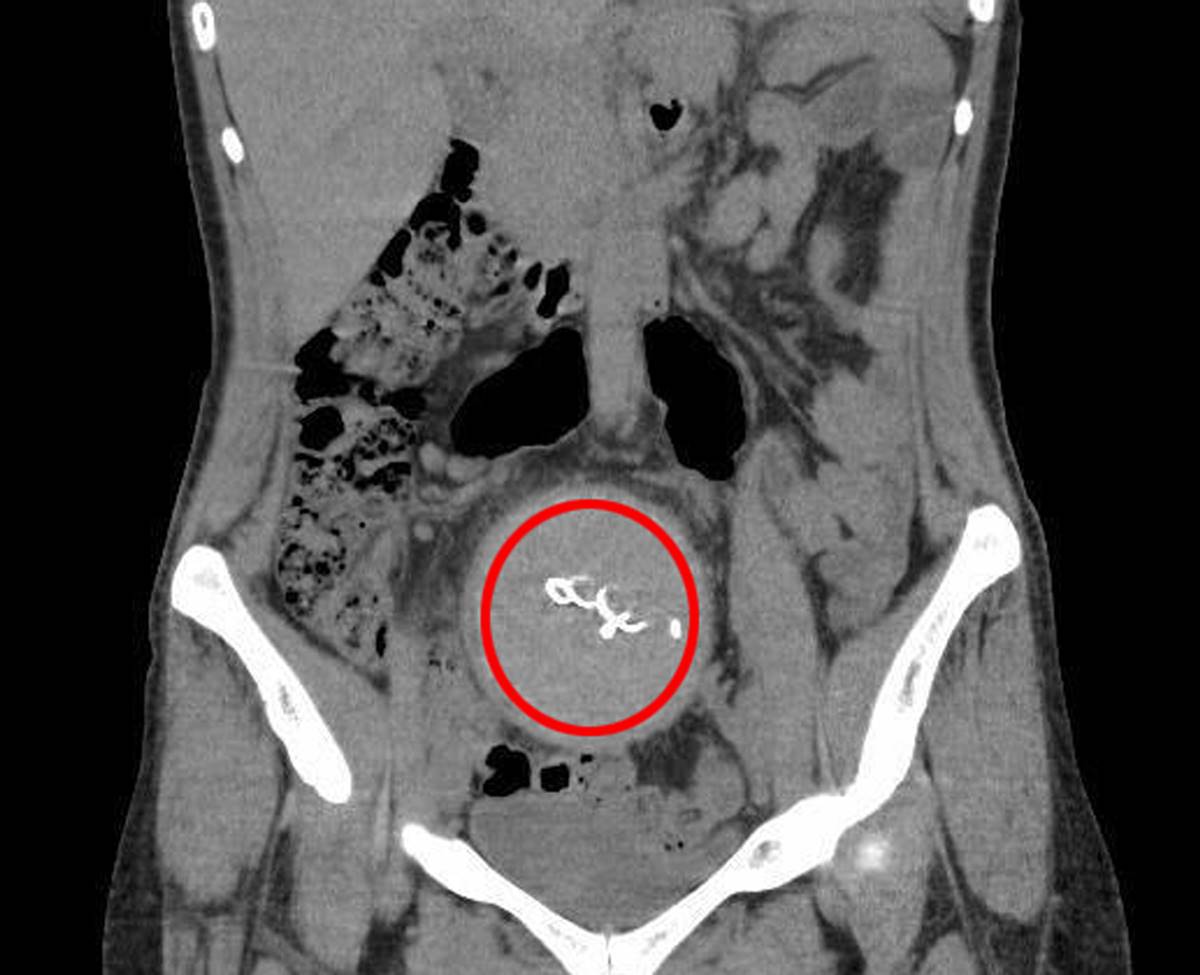

Burada yapılan kontrolde doktor acil tomografi çektirmesini istedi. Çekilen tomografide Y.S.'nin vücudunda doğum sonrası unutulan sargı bezi görüldü. Büyük şok yaşayan Y.S., iki yıldır yaşadığı ağrılara ihmalin sebep olduğunu öğrendi. Y.S.'nin karnında unutulan yaklaşık 30 santimetre uzunluğundaki gazlı bez ameliyatla çıkarıldı. Y.S., hastane ve doktor hakkında hukuki süreci başlatması için avukatı Hasret Baş’a başvurdu.

Çok zor günler yaşadığını belirten Y.S., iki yıl boyunca ağrılarının ve ara ara iltihap akışının devam ettiğini söyledi. Y.S., "Farklı hastanelere de başvurdum ancak kimse bir teşhis koyamadı. En son Antalya Eğitim ve Araştırma Hastanesi'ne başvurdum. Burada bana doğum sırasında vücudumda sargı bezi kaldığı söylendi. İlk doğum yaptığımda 10 gün boyunca ağrılarım yüzünden çocuğumu kucağıma bile alamamıştım" diye konuştu.